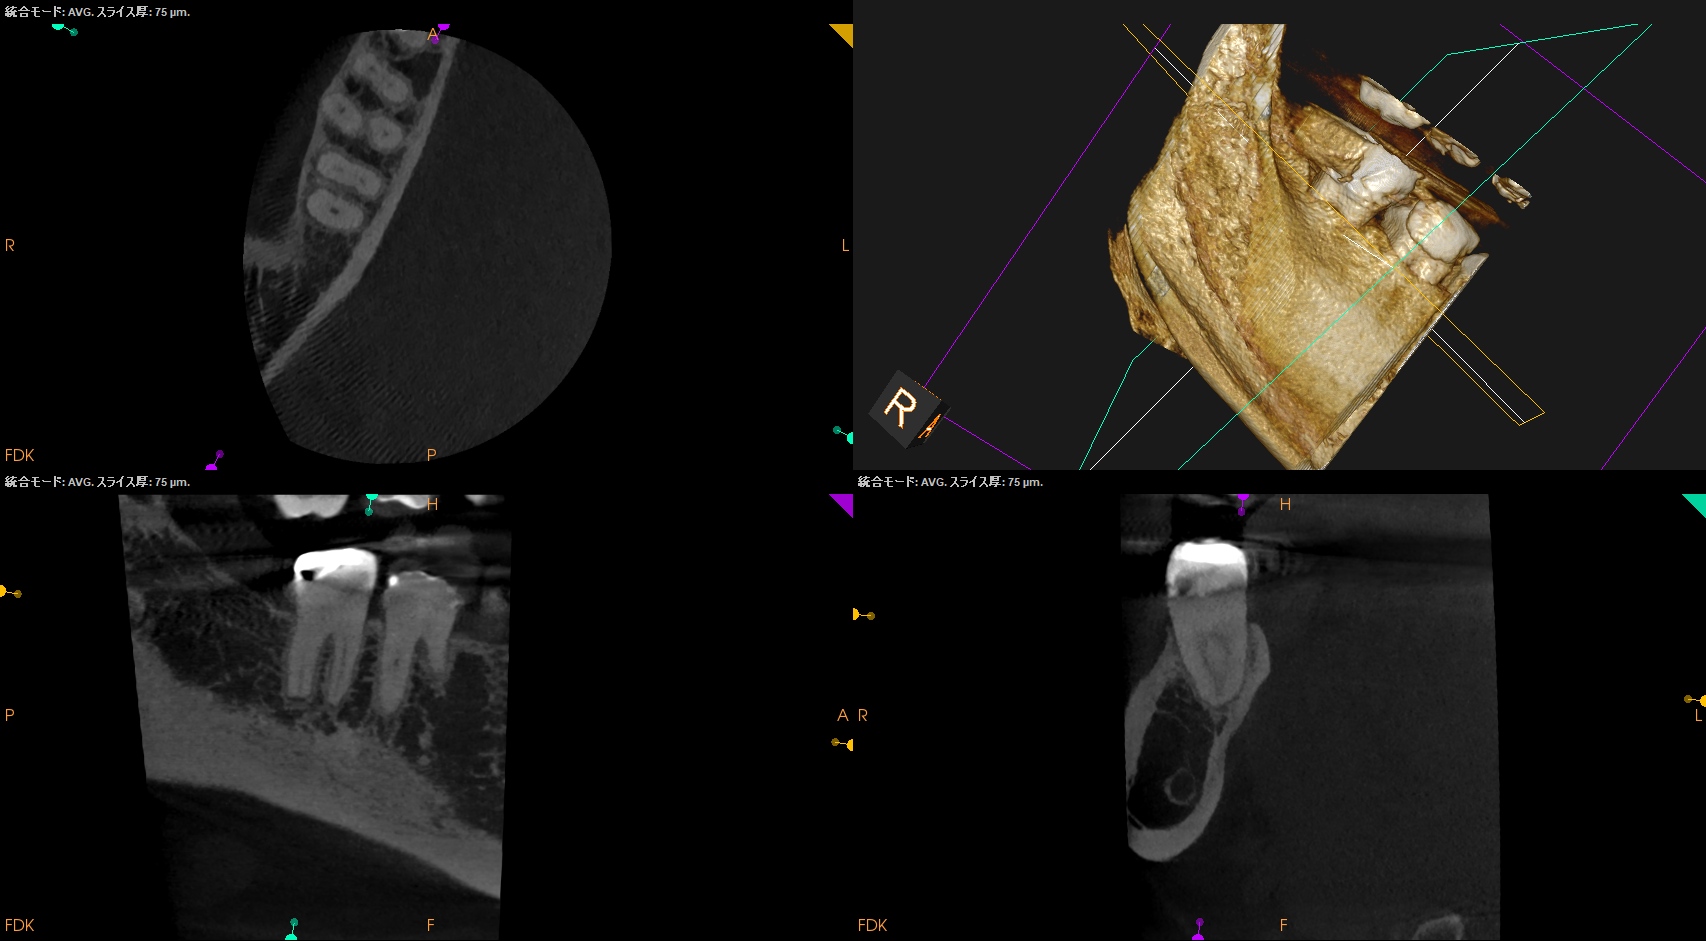

以下のように根管形成した。

Dは#60.02で形成しても出血がペーパーポイントに見られたためにProTaper Gold F5まで形成した。

ML,MBは合流していることが多いと言う解剖学的情報をもとに以下のように合流部分をチェックした。

問題はないだろう。